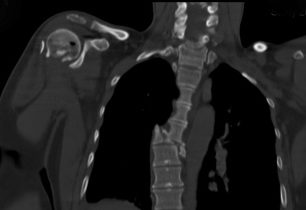

Druhá část výpovědi ženy, která přežila pád v Himálajích: zlomené obratle a problémy s pojišťovnou